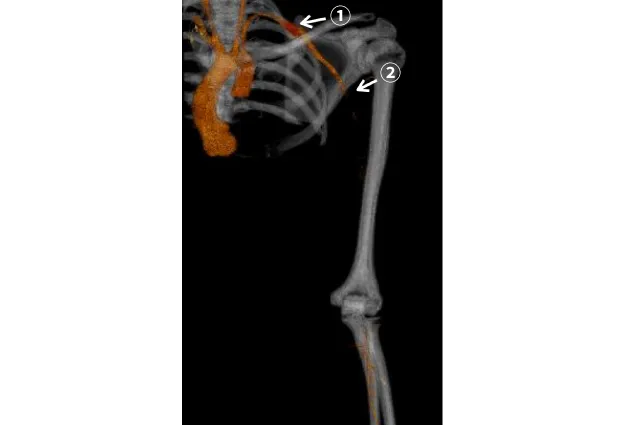

aTOS自体の診断は鎖骨下動脈狭窄・閉塞による上肢虚血症状〈前述「診断」aTOS 図2〉や鎖骨下動脈瘤が塞栓源となる上肢や手の動脈塞栓症〈前述「診断」aTOS 図4〉に伴って発見されます。上肢の急性動脈閉塞症〈図18〉のほか、鎖骨下動脈瘤の発症がみられ〈図19〉、鎖骨下動脈瘤からの椎骨動脈塞栓症により脳梗塞を発症する例もあります。

外科治療では、鎖骨上と鎖骨下の2か所に切開を加えます。鎖骨下動脈病変は頚肋に起因する例が多く、頚肋を認める場合には、まずこれを切除します〈図18a,b,c〉。さらに通常、第一肋骨切除および前・中斜角筋切離を行います。

加えて、鎖骨下動脈瘤や鎖骨下動脈〜上肢動脈の狭窄・閉塞に対しては〈図19〉、鎖骨下動脈置換術、あるいは鎖骨下動脈〜上肢動脈バイパス術(血管移植術)による血行再建を行います〈図20,21〉。

図18

図18. 頚肋を伴う左動脈性胸郭出口症候群

• 左頚肋typeIII XP(矢印)

• 左頚肋typeIII CT(矢印)

• 鎖骨上切開創からみた第一肋骨(矢印)とそれに付着するtypeIIIの頚肋(太矢印)